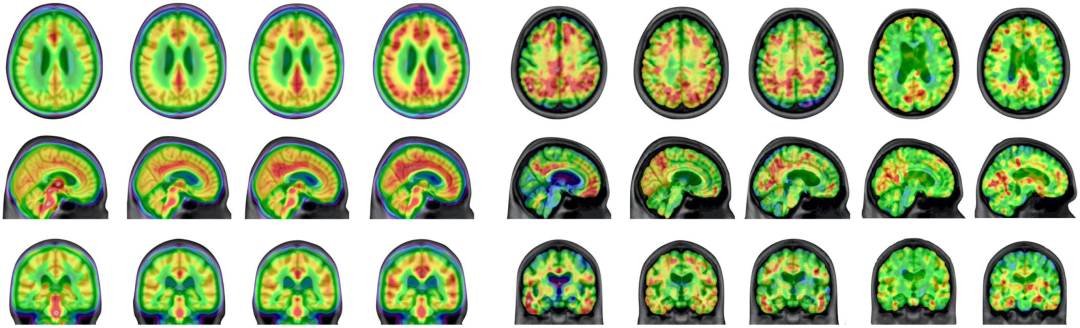

他们招募了130多名处于衰老或者AD不同阶段的参与者,用PET成像技术研究他们大脑的小胶质细胞激活(神经炎症)、Aβ和Tau,结果发现Tau蛋白的扩散是小胶质细胞激活驱动的,小胶质细胞激活是连接Aβ病理和Tau病理的纽带。

在这项研究中,Pascoal团队用显像剂[11C]PBR28量化大脑的小胶质细胞激活,用[18F]AZD4694量化Aβ病理,用[18F]MK-6240量化Tau病理。

最终一共有130人参与了本研究,这些人具有完整的认知、磁共振成像(MRI)和PET基线数据,包括22个认知正常(CU)的年轻人,64个认知正常的老年人,28个轻度认知障碍(MCI)患者和16个AD患者。